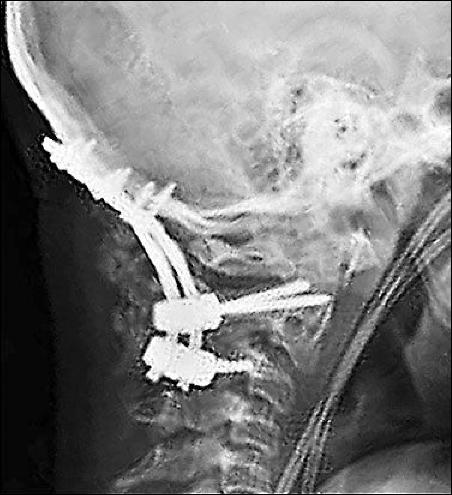

鈦合金的鋼釘被植入了頸椎

最后再?gòu)?qiáng)調(diào)一句,如果你頸椎痛的已經(jīng)不行了,千萬(wàn)別做手術(shù),我可以負(fù)責(zé)任地說(shuō),做一個(gè)完蛋一個(gè)。我曾經(jīng)見(jiàn)過(guò)一個(gè)30多歲的公司老總,胖的不行,脖子里打了好幾根鈦合金的鋼釘,現(xiàn)在基本上是“廢人”一個(gè)了。當(dāng)我給他講完這頸椎病的事,他后悔不已。本來(lái)很簡(jiǎn)單的事,醫(yī)生為了掙錢,就給他打了鋼釘,把他變成了“廢人“。但是,當(dāng)有人告訴你,刮痧可以治頸椎病時(shí),你會(huì)相信嗎?很少有人會(huì)信,為什么呢?因?yàn)榭粗蝗绱蜾撫攣?lái)的有技術(shù)含量。所以,人就是這么無(wú)知,被忽悠了,最后搞的是人財(cái)兩空。